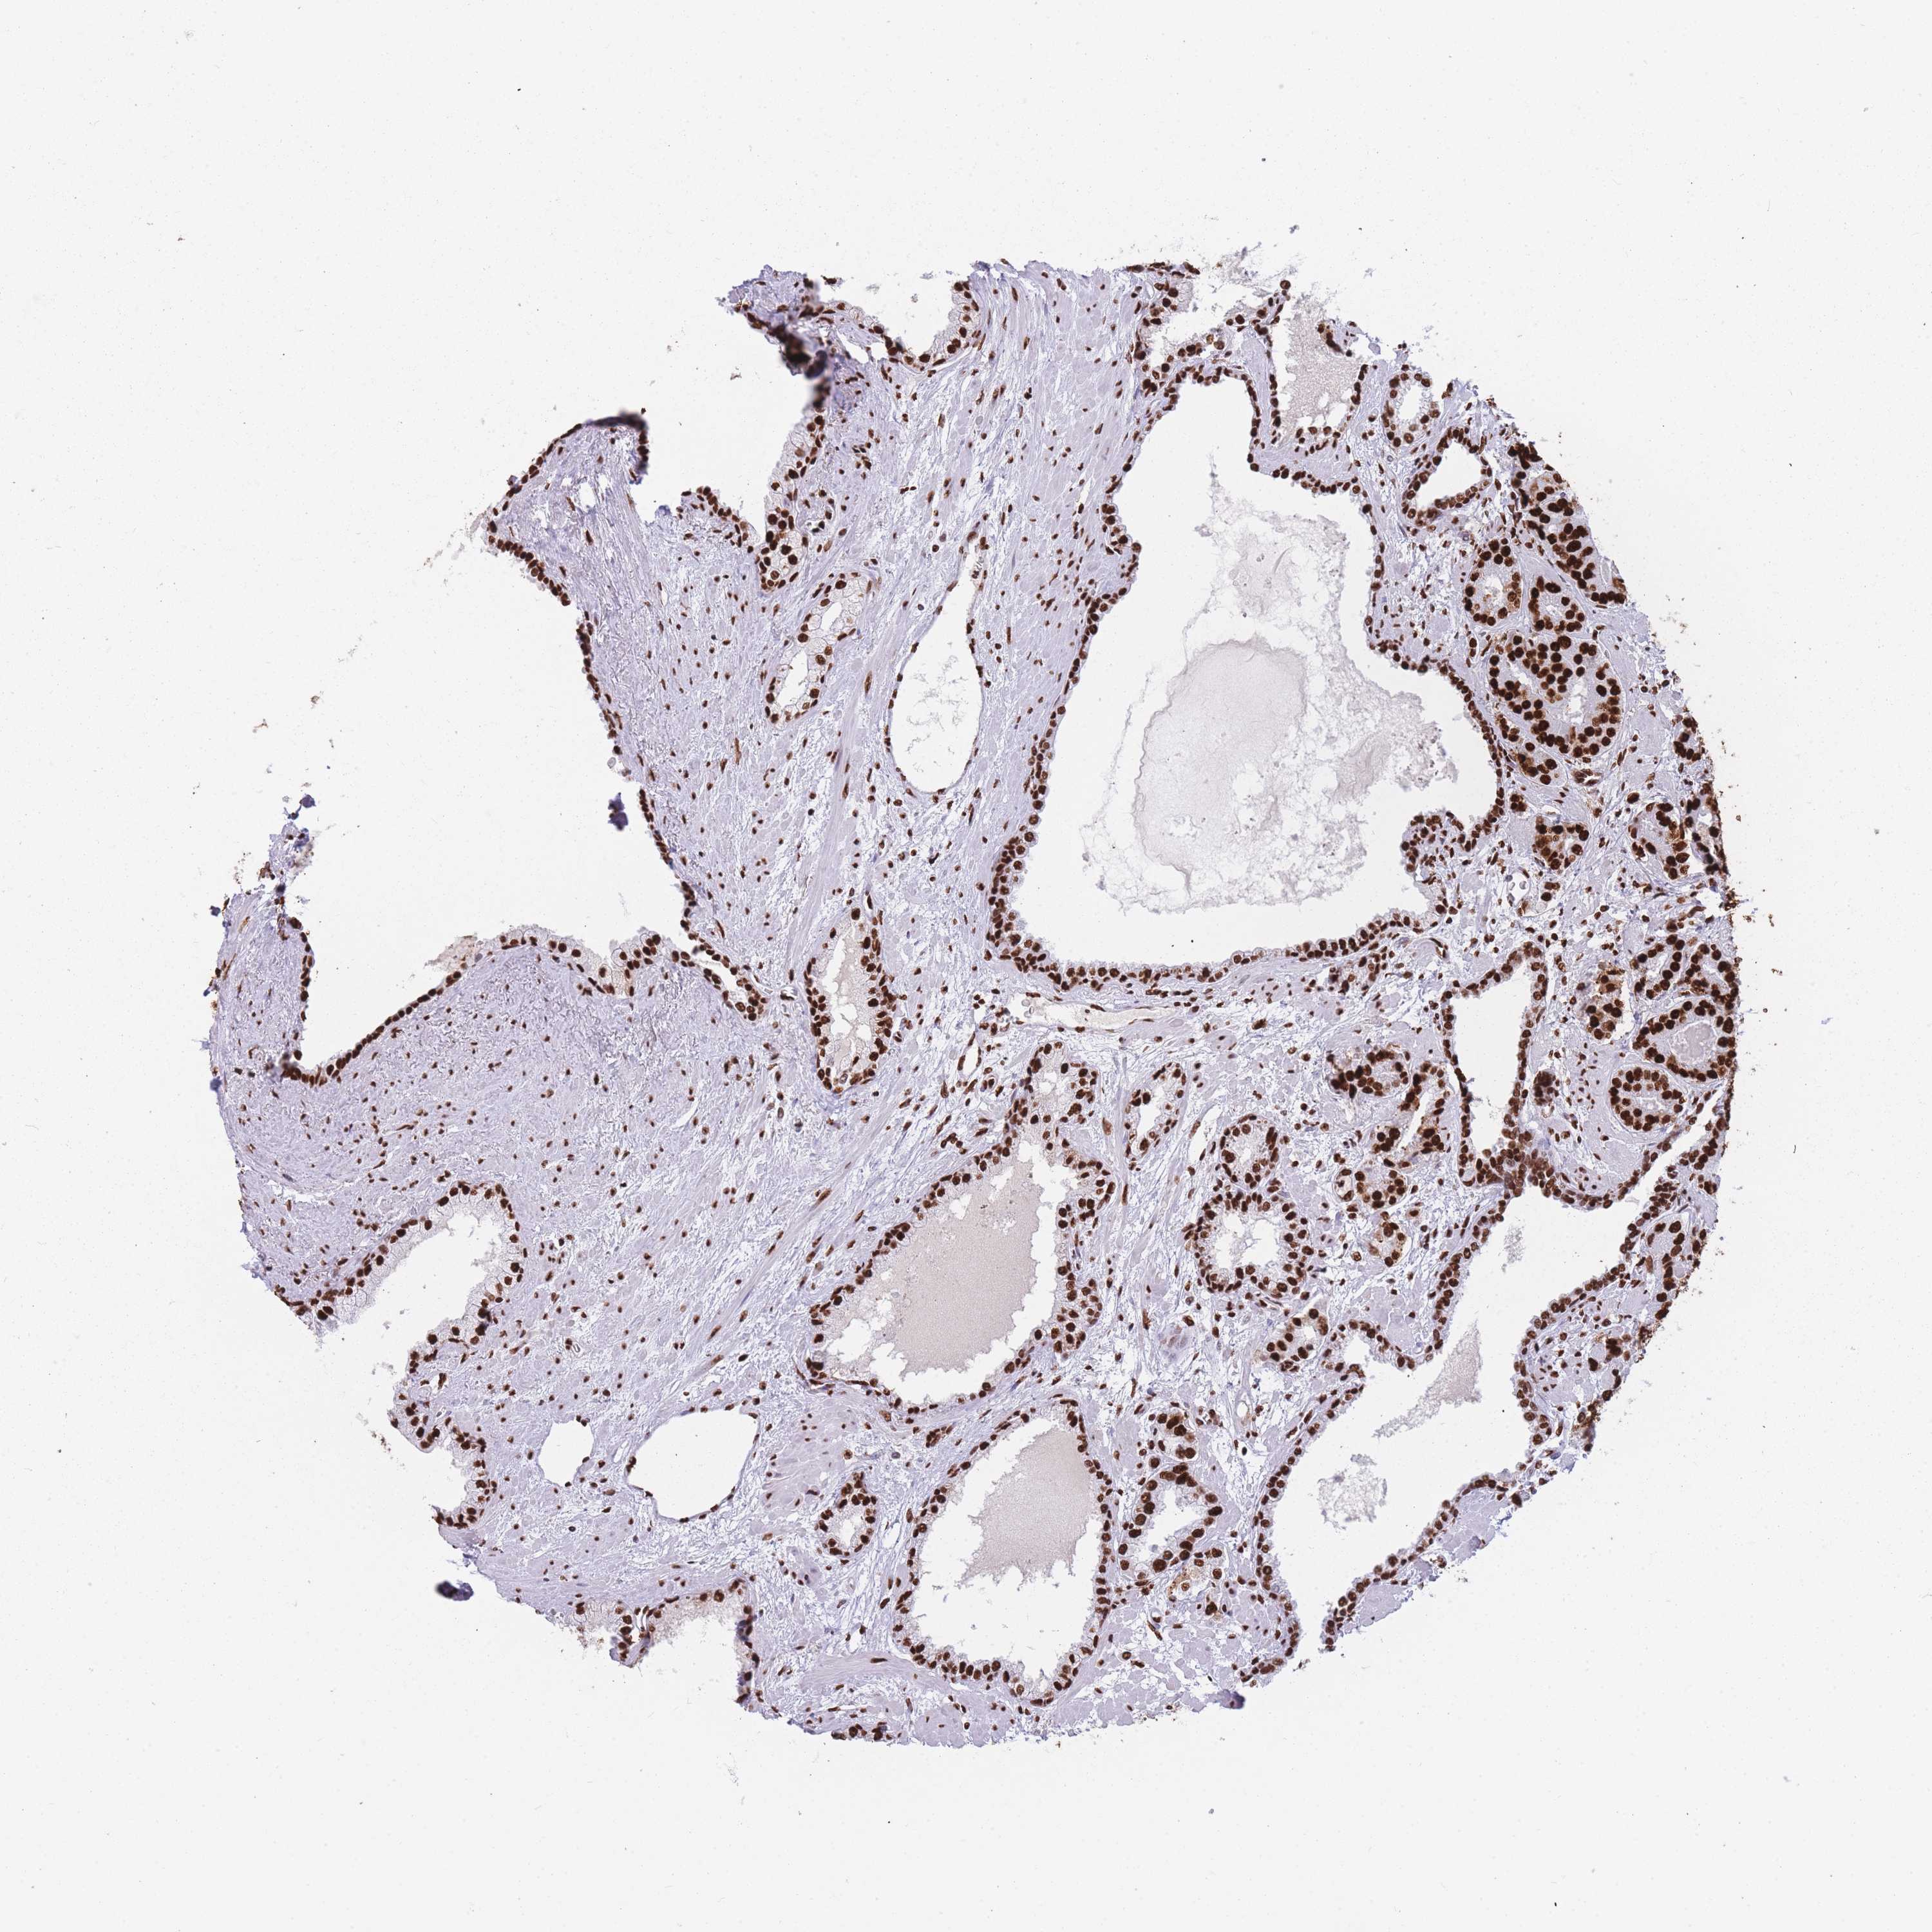

PROSTATE CANCER - Protein expressioni

A mouse-over function shows sample information and annotation data. Click on an image to view it in a full screen mode. Samples can be filtered based on level of antibody staining by selecting one or several of the following categories: high, medium, low and not detected. The assay and annotation is described here.

Antibody stainingi

Antibody staining in the annotated cell types in the current human tissue is reported as not detected, low, medium, or high, based on conventional immunohistochemistry profiling in selected tissues. This score is based on the combination of the staining intensity and fraction of stained cells.

Each image is clickable and will lead to virtual microscopy that enables deeper exploration of all samples and also displays staining intensity scores, fraction scores and subcellular localization as well as patient and tissue information for each sample.

Antibody HPA046290

Antibody HPA049475

Antibody CAB046477

Staining

High

Medium

Low

Not detected

Intensity

Strong

Moderate

Weak

Negative

Quantity

>75%

75%-25%

<25%

None

Location

Nuclear

Cytoplasmic/membranous

Cytoplasmic/membranous,nuclear

Adenocarcinoma, High grade

Adenocarcinoma, Low grade